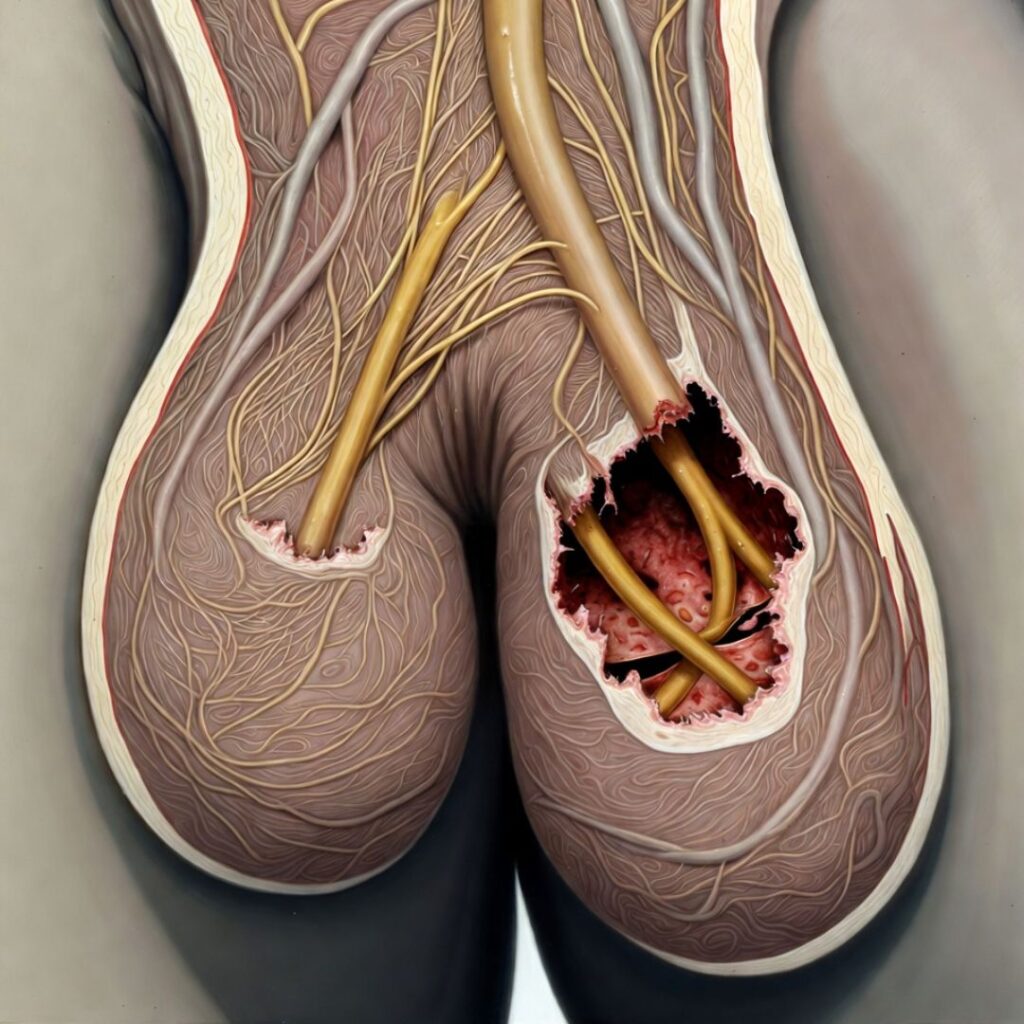

Deep inside your pelvis — wrapping around your prostate gland, threading along the base of your penis, and extending in a dense web of fibres all the way to the nerve endings at its tip — there is a network of nerves. Medical textbooks call it the cavernous nerve system. Think of it, for the purposes of this conversation, as the electrical wiring of your sexuality.

When you experience arousal — when your brain processes a touch, an image, a memory, a smell — it sends an electrical signal. That signal travels down your spinal cord, branches out through your pelvic nerves, and arrives at the cavernous nerve network. From there, the nerves release a chemical called nitric oxide. Nitric oxide causes the smooth muscle tissue inside the penis to relax. Blood floods in. The tissue expands. You have an erection.

The nerves in the cavernous network are coated in a protective layer called the myelin sheath.

This sheath does two things: it insulates the nerve fibre so the electrical signal doesn’t leak out, and it accelerates the signal so it arrives at its destination with full strength. Without an intact myelin sheath, the signal weakens. It slows. It gets lost before it reaches its target.

Over years — and this happens gradually, so gradually that most men don’t notice until the damage is done — the myelin sheath around the cavernous nerves begins to degrade.

The signals your brain sends become whispers instead of commands. The nerve endings stop releasing nitric oxide efficiently. The smooth muscle doesn’t relax. The blood doesn’t flood in.